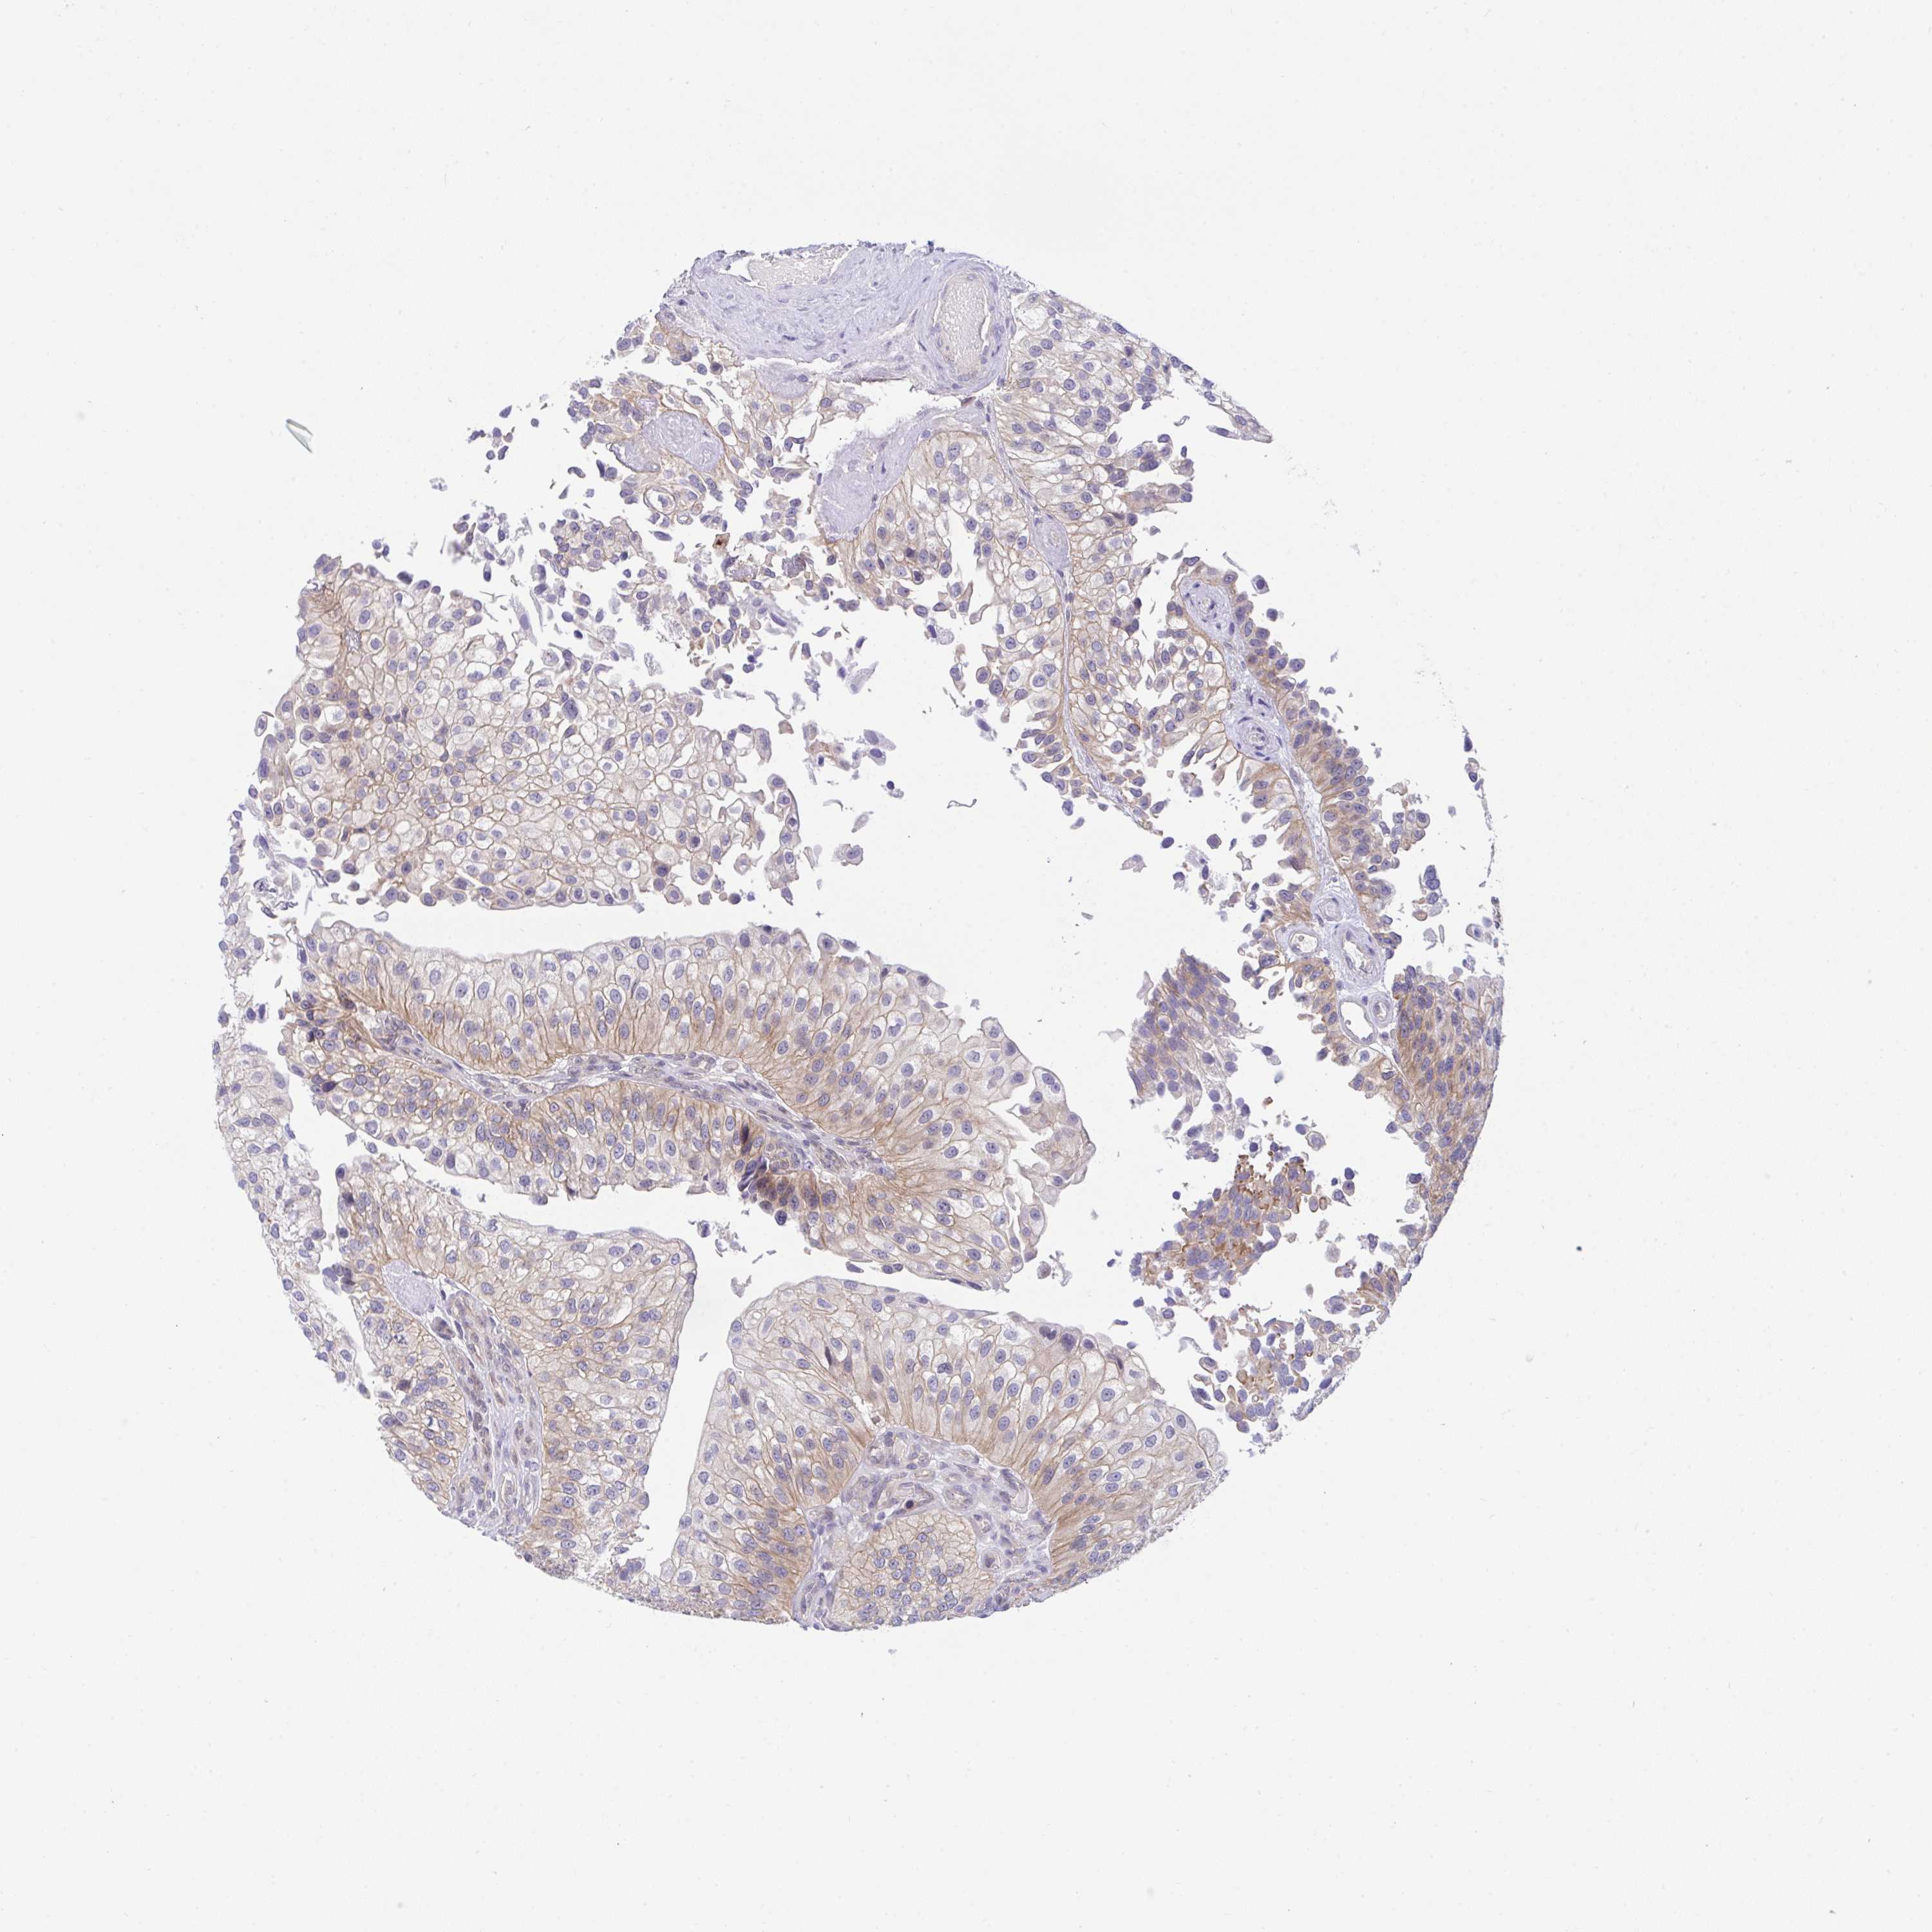

UROTHELIAL CANCER - Protein expressioni

A mouse-over function shows sample information and annotation data. Click on an image to view it in a full screen mode. Samples can be filtered based on level of antibody staining by selecting one or several of the following categories: high, medium, low and not detected. The assay and annotation is described here.

Antibody stainingi

Antibody staining in the annotated cell types in the current human tissue is reported as not detected, low, medium, or high, based on conventional immunohistochemistry profiling in selected tissues. This score is based on the combination of the staining intensity and fraction of stained cells.

Each image is clickable and will lead to virtual microscopy that enables deeper exploration of all samples and also displays staining intensity scores, fraction scores and subcellular localization as well as patient and tissue information for each sample.

Antibody HPA059444

Staining

High

Medium

Low

Not detected

Intensity

Strong

Moderate

Weak

Negative

Quantity

>75%

75%-25%

<25%

None

Location

Nuclear

Cytoplasmic/membranous

Cytoplasmic/membranous,nuclear

Urothelial carcinoma, High grade

Urothelial carcinoma, NOS

Urothelial carcinoma, Low grade